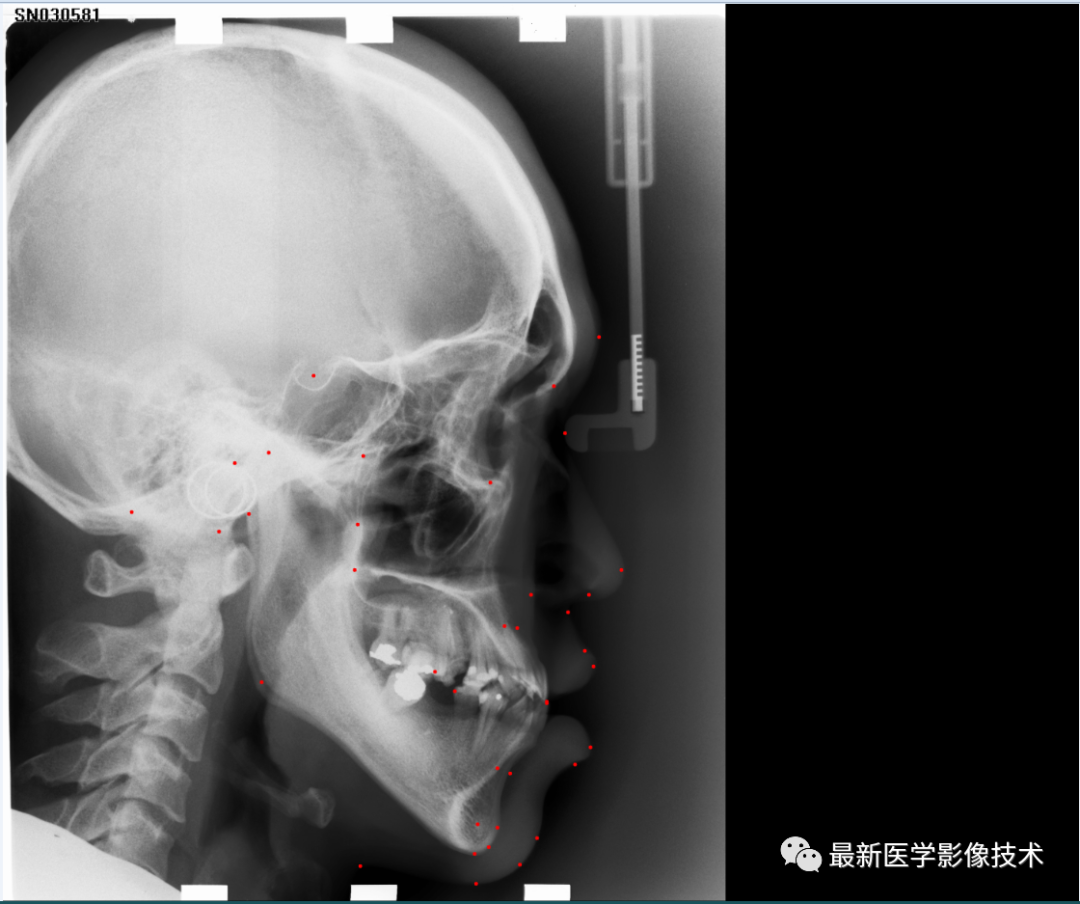

头部测量分析是一项基础检查,常用于正畸和正颌领域。分析过程中的关键操作是从侧位头颅照片中标记颅面标志,这提供了患者颅面状况的诊断信息并影响治疗计划决策。由于颅骨的 X 射线成像质量和解剖类型的个体差异,要在侧位头颅图中以高精度可靠地定位标志并不容易。可靠的标注通常需要经验丰富的医生,即使对于经验丰富的正畸医生来说,手动识别这些标记也是一个耗时的过程。

头部测量38个关键点自动检测。

通过使用更多的标注来扩展现有基准数据集,将获得多样化的头颅测量标记检测数据集,其中包括来自 3 个医疗中心的 600 张 X 射线图像以及所有病例的 38 个颅面标记点。